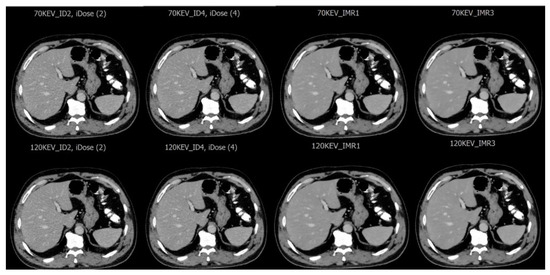

3.1. Imaging Assessment of Metastatic and Hemangioma Cases

3.2. Evaluation for Patients with Fatty Liver Disease

3.3. Image Quality Evaluation Based on Radiologist